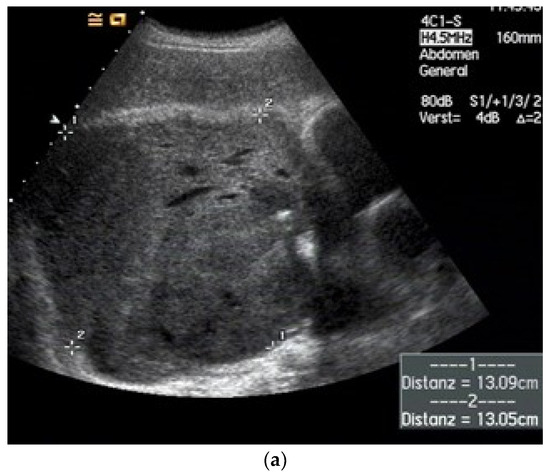

| Lipoma | Homogeneous or heterogeneous hypoechoic mass without any calcification or internal vascular supply. Slight heterogenous hypoenhancement on CEUS. |